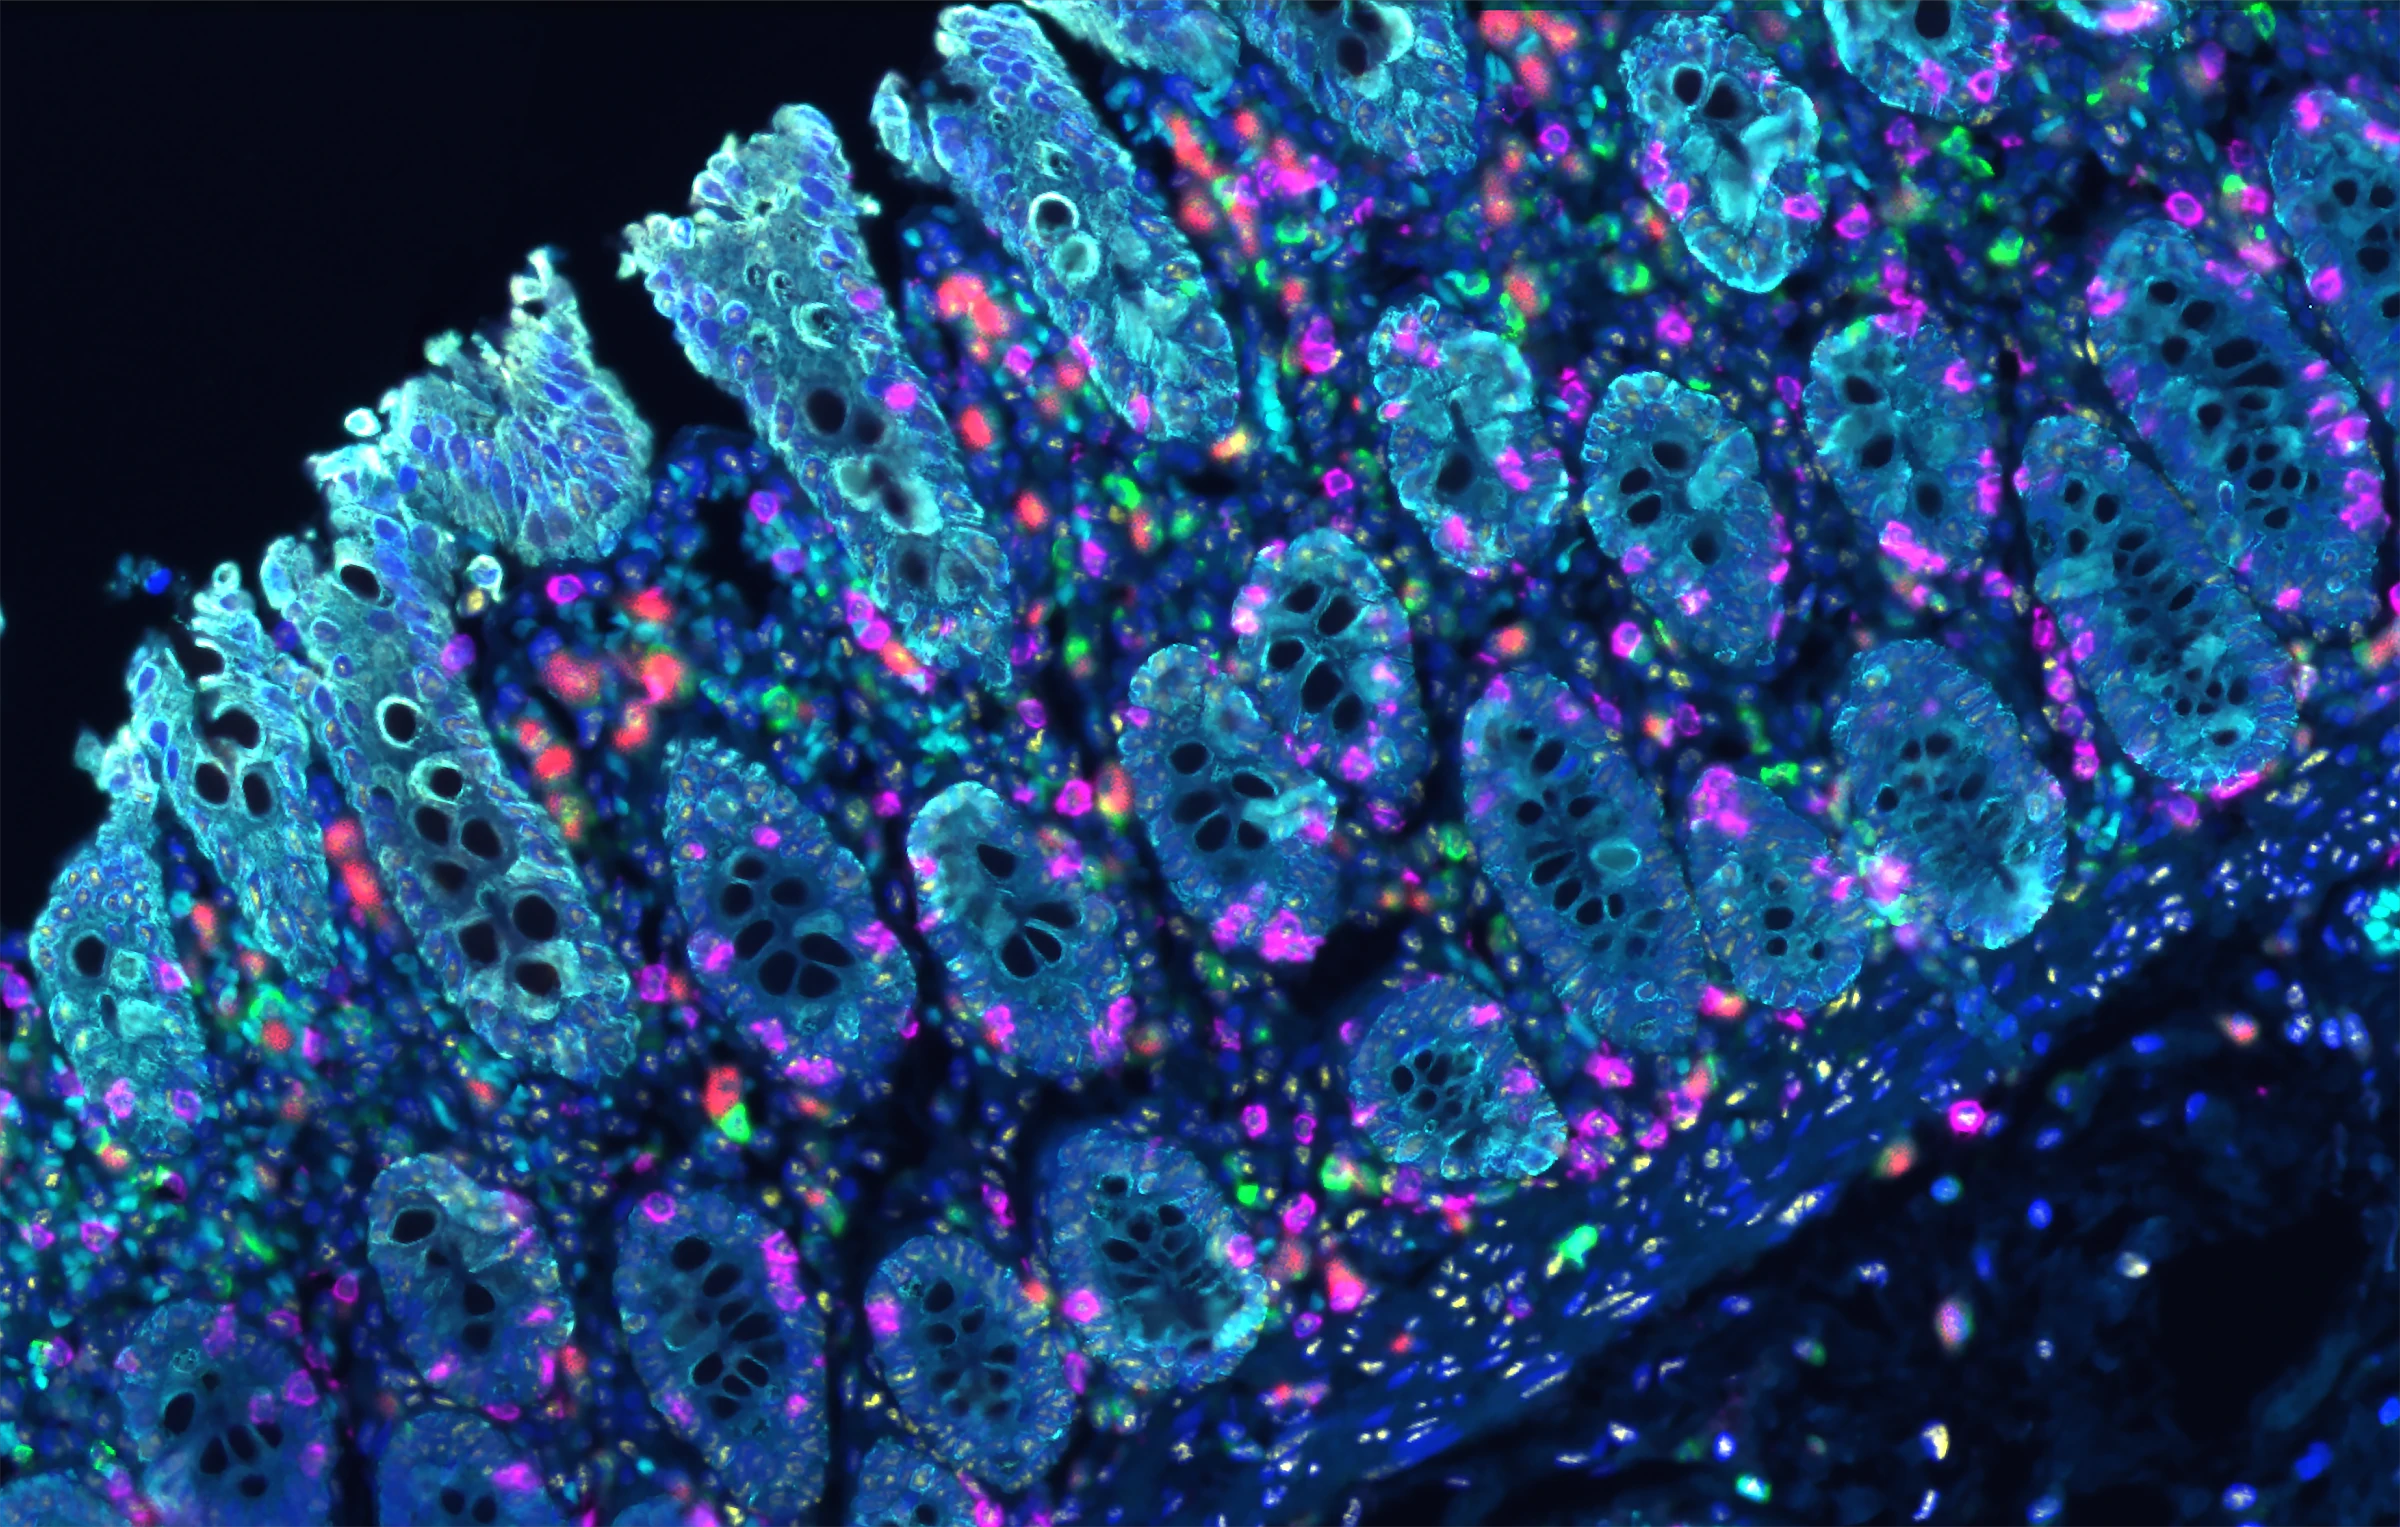

免疫组化抗体

达科为提供200+种IHC一抗产品,有鼠源和兔源两类抗体,手工和仪器均可适配,一抗产品均为单克隆抗体,能够确保与目标抗原结合的特异性,同时一抗具有极高的灵敏度,可以在样本中检测到低表达水平的目标抗原,并获取可靠的结果。

达科为提供200+种IHC一抗产品,有鼠源和兔源两类抗体,手工和仪器均可适配,一抗产品均为单克隆抗体,能够确保与目标抗原结合的特异性,同时一抗具有极高的灵敏度,可以在样本中检测到低表达水平的目标抗原,并获取可靠的结果。